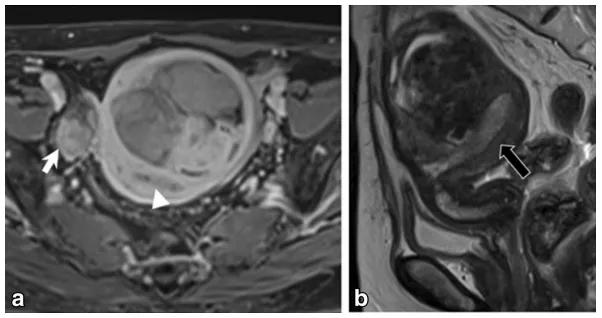

女,68 岁,左卵巢 Brenner 瘤。T2WI 显示左侧卵巢巨大低信号肿物(图 a),CT 扫描显示 8 年后肿物增大、多发钙化、发生囊变(图 b)。